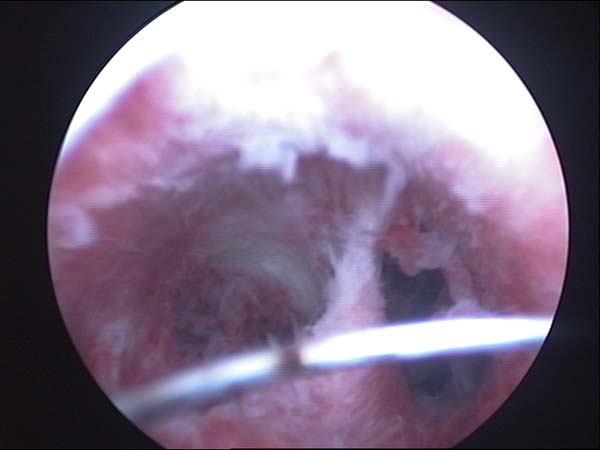

- Photos de l’hystéroscopie

Photos de l’hystéroscopie | Dr N Layyous